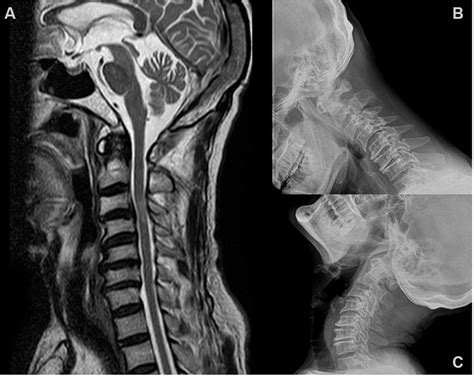

The cervical spine MRI stands as one of the most sophisticated diagnostic tools available in modern medicine for evaluating neck pain, neurological symptoms, and spinal abnormalities. When persistent discomfort or radiating numbness begins to interfere with your daily life, your healthcare provider may recommend this non-invasive imaging technique to peer into the delicate structure of your neck. By utilizing powerful magnets and radio waves rather than ionizing radiation, a cervical spine MRI produces exceptionally detailed cross-sectional images of the seven vertebrae, intervertebral discs, spinal cord, and surrounding soft tissues. Understanding what this procedure entails can significantly reduce patient anxiety and ensure you are well-prepared for your diagnostic journey.

The cervical spine is a marvel of biological engineering, supporting the weight of the head while allowing for a wide range of motion. It is composed of seven vertebrae (C1 to C7) separated by shock-absorbing discs. Because the spinal cord passes through the central canal of these vertebrae, even minor structural shifts can lead to significant health issues. A cervical spine MRI is primarily used to identify conditions that physical exams or standard X-rays might miss, such as nerve root compression or subtle tissue inflammation.

Once the cervical spine MRI is complete, the images are sent to a radiologist—a physician specialized in interpreting medical scans. They will scrutinize the images for signs of stenosis, herniation, or signal changes in the spinal cord. A formal report is then generated and sent to your referring physician. You should schedule a follow-up appointment to discuss these findings in detail, as the clinical significance of a finding depends on your specific symptoms, medical history, and physical examination results.

The primary advantage of choosing a cervical spine MRI over other modalities, such as a CT scan, is the superior soft-tissue contrast. Because the spinal cord, ligaments, and nerves are composed of soft tissues, MRI provides the highest level of detail for these structures. Furthermore, the absence of ionizing radiation makes it a safer long-term option for patients who may require serial imaging to monitor degenerative conditions over several years.